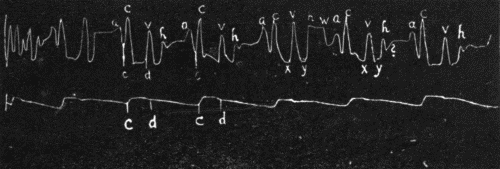

38. Right side of the heart showing distribution of the two vagus nerves127

39. Normal electrocardiogram128

40. Auricular flutter132

41. Auricular fibrillation134

[22]

42. Auricular fibrillation134

43. Pulse deficit135

44. Ventricular fibrillation137

45. Auricular extrasystoles139

46. Ventricular extrasystole139

47. Delayed conduction141

48. Partial heart block141

49. Complete heart block142

50. Alternating periods of sinus rhythm and auriculoventricular rhythm144

51. Auriculoventricular or "nodal" rhythm144

52. Influence of mechanical pressure on the right vagus nerve144

53. Schematic distribution of right and left vagus145